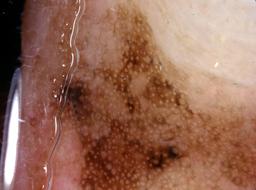

{

"age_approx": 55,

"anatom_site_general": "posterior torso",

"concomitant_biopsy": true,

"dermoscopic_type": "contact non-polarized",

"diagnosis_1": "Malignant",

"diagnosis_2": "Malignant melanocytic proliferations (Melanoma)",

"diagnosis_3": "Melanoma, NOS",

"diagnosis_confirm_type": "histopathology",

"image_type": "dermoscopic",

"lesion_id": "IL_6864076",

"melanocytic": true,

"patient_id": "IP_4659192",

"sex": "female"